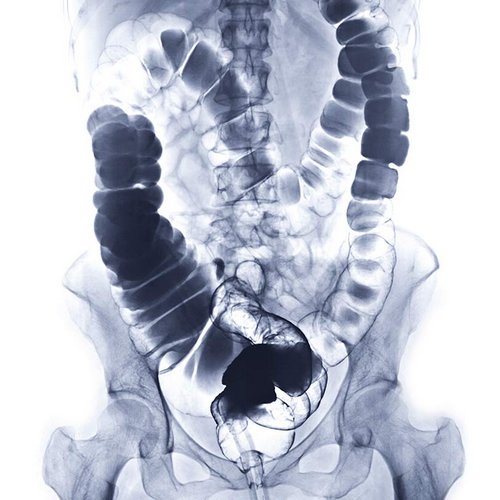

We have a huge number of cases with different modalities and regions

By Modality

By Region